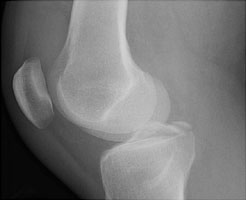

Tibial Fracture (PCL Avulsion)

The anterior cruciate ligament attaches on or adjacent to the medial tibial spine of the intercondylar eminence while the posterior cruciate ligament attaches to the posterior surface of the tibia. Fractures of the medial tubercle (spine) therefore indicate that the ACL has been likely be torn from the tibia.

- Click on the image for a larger versionBLateral radiograph of the knee. This shows the radiographic appearance of the MRI findings.